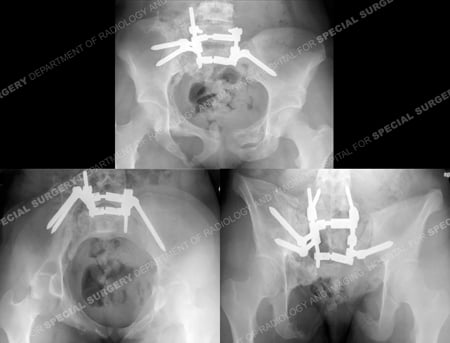

Radiograph following anterior pelvic external fixation (top image), anteroposterior radiograph following fracture reduction and placement of spino-pelvic fixation (middle image), and postoperative CT scan images showing acceptable reduction and hardware positioning (bottom images).